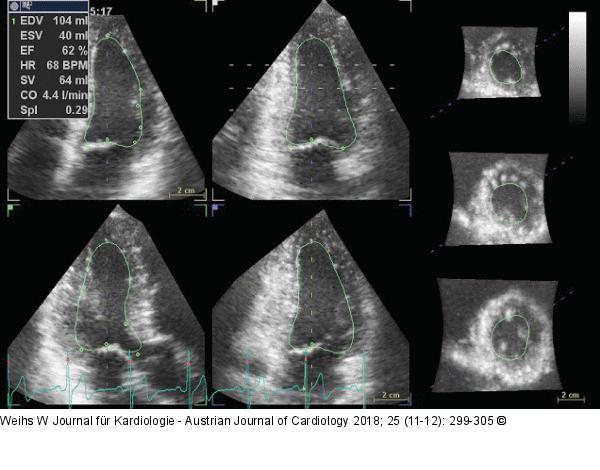

Abbildung 3: LV-Volumina - LV-EF Semiautomatische Quantifizierung des LV-Volumina und -EF im 3DE. |

Semiautomatische Quantifizierung des LV-Volumina und -EF im 3DE. |